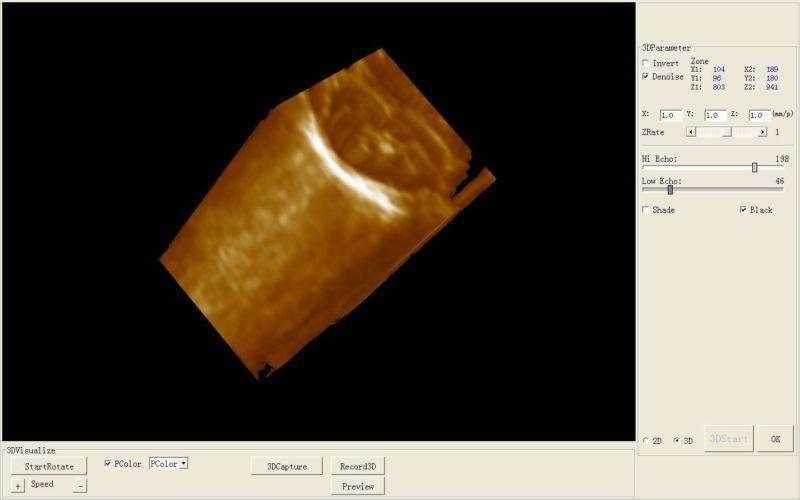

Model: RUS-6000V

Display modes: B, B+B, B+M, M, 4B

Display/ Monitor/ Screen: 10.1â high-resolution TFT LCD

Multi-frequency: Image magnification: x0.8, x1.0, x1.2, x1.5, x2.0

Pseudo color processor:7 color: Video output: PAL-D, VGA . USB port

Optional: linear/transvaginal/micro-cardiac/rectal/printer